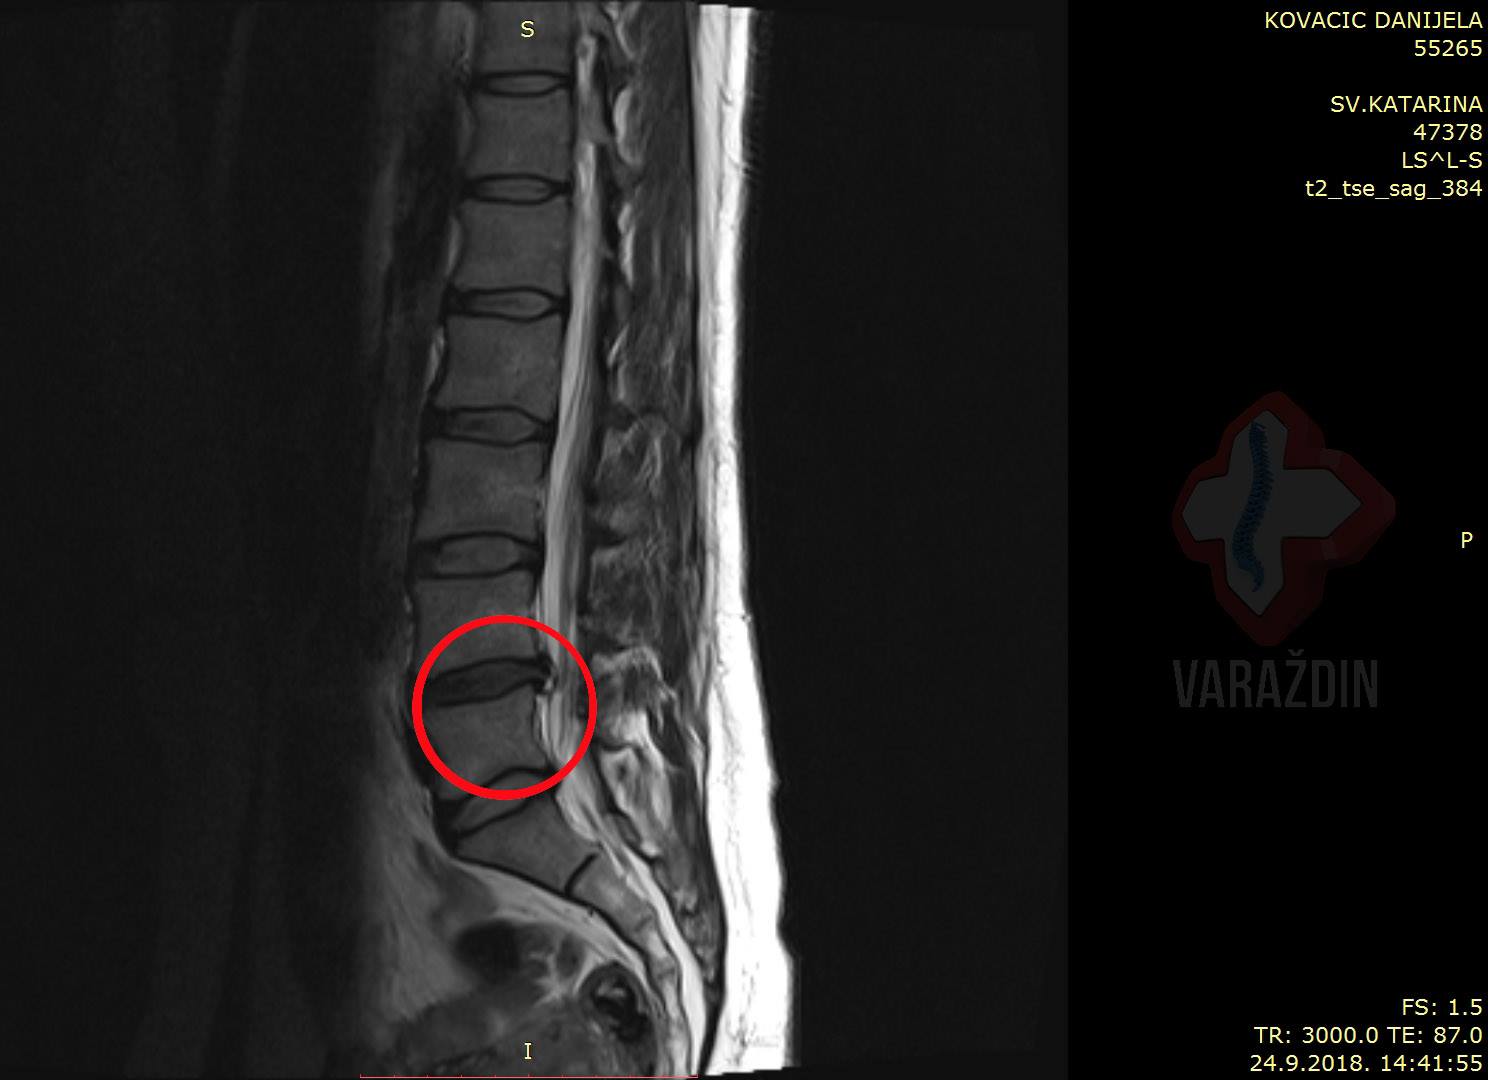

Gospođa Danijela Kovačić prvi puta javila nam se

i posjetila Nado centar zdravlja Varaždin nakon

kiropraktičarskog zahvata nakon kojeg se stanje pogoršalo. Uvidom

u MR snimku uočena je prisutna ekstruzija diska

L4-L5 – dakle – predoperativnog stanja. Od boli

je bila ograničena na ležanje na lijevom boku. Zbog straha od

operacije i nade u potencijalno poboljšanje stanja uspjeli smo

disk dovesti do protruzije zbog čega je došlo do regresivnog

stanja diska između diska L4 i L5. Do potpune

regresija kao što se i vidi na pratećim slikama nije

došlo, ali bol je nestala.